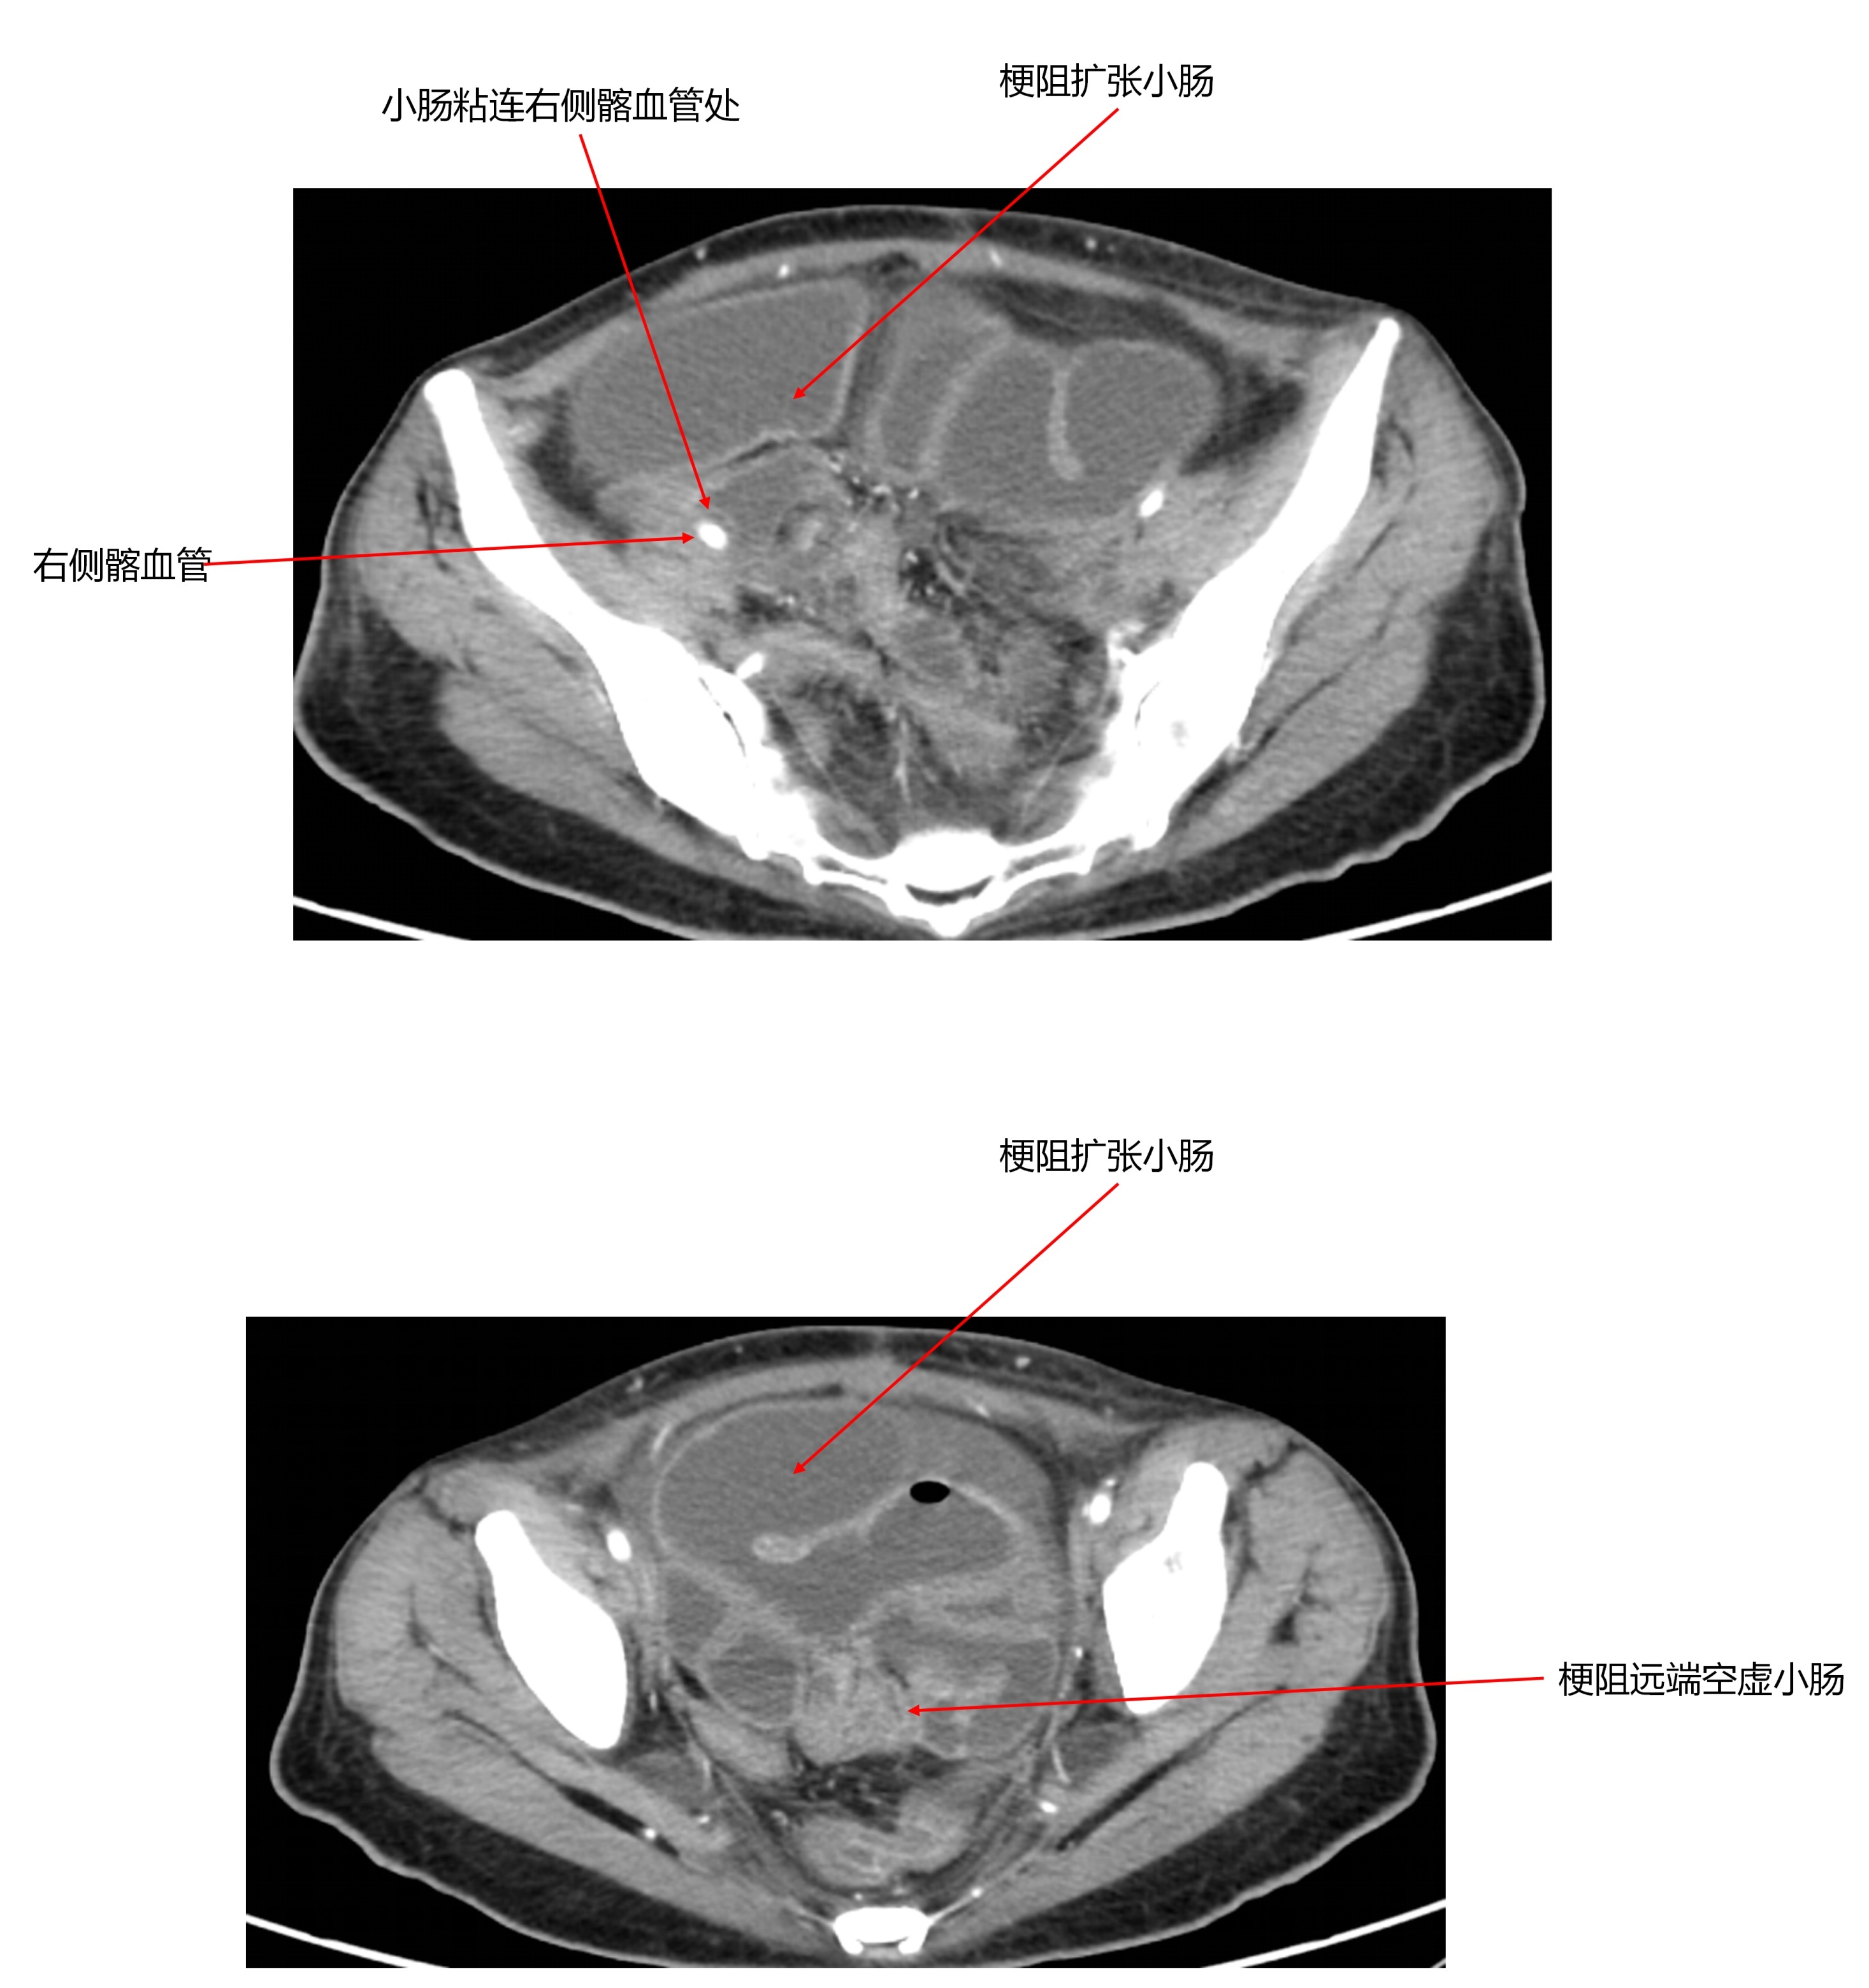

近日,北京清华长庚医院胃肠外科接诊的一例患者,就是如此。身高167cm,体重却仅有80斤……原来她曾因宫颈癌接受子宫切除术,术后进行了放、化疗。然而从2023年4月开始,她反复腹痛、腹胀和便秘,出现肠梗阻症状,保守治疗效果不佳,体重显著下降。术前腹部CT提示患者腹腔粘连严重,小肠梗阻且位置不佳。

在一段时间小肠减压和营养支持后,李元新团队开展达芬奇机器人辅助手术。术前,团队精心规划入路设计和手术路径,考虑到手术主要操作区域位于右侧腹部和盆腔,团队将机器人置于患者右侧,在脐左上方4cm处建立主操作通道,并确保术中各机械臂之间不会发生干扰。历时近6小时,李元新小心分离小肠与盆腔和髂血管间粘连,谨慎切除放射性损伤的部分结肠和小肠,随后完成健康小肠与升结肠侧侧吻合等复杂操作,术后没有发生中重度并发症。术后第三天患者恢复流食,九天出院,患者术后回访,体重增重了30斤。